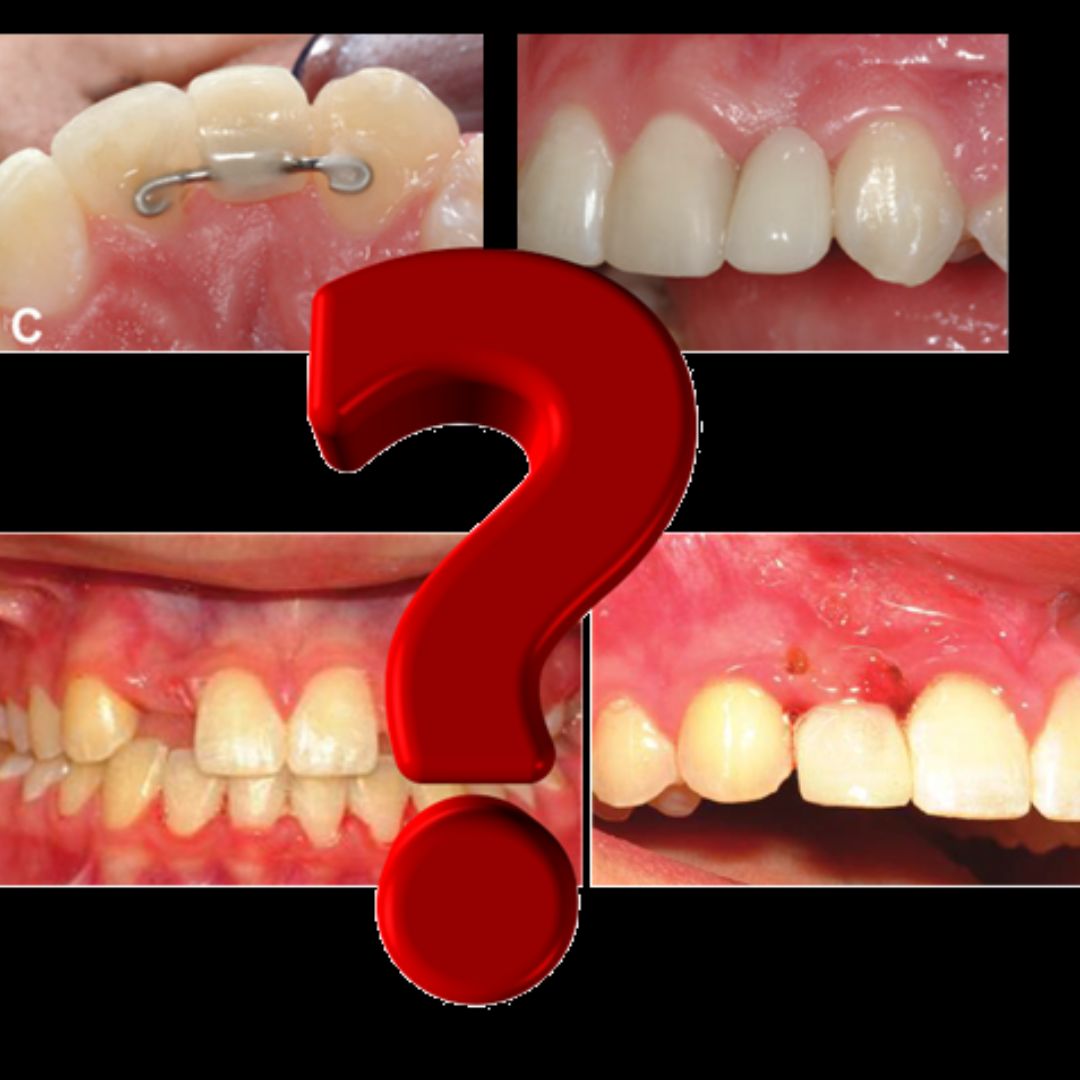

Ortodonticamente, podemos adotar 2 caminhos terapêuticos: o fechamento de espaço, por meio da mesialização dos dentes posteriores, ou a abertura de espaço, mantendo ou criando espaço para futura reabilitação protética, geralmente com implantes osseointegrados. Porém, a inserção de implantes osseointegrados requer que o paciente já tenha finalizado o crescimento ósseo. Em consequência, uma vez optado pela segunda abordagem. após o tratamento ortodôntico, precisamos preservar o espaço obtido através de próteses removíveis, próteses fixas ou, como sugerido mais recentemente, através de reabilitação com mini-implante ortodôntico e coroa estética (ROSA, 2022).

Entretanto, existe controvérsia em relação à inserção do mini-implante em áreas edêntula, pois, para uns, o mini-implante tem a capacidade de contribuir com a manutenção do osso alveolar na região edêntula (COPE, 2014), mas para outros, o osso alveolar perfurado pelo mini-implante não acompanha o crescimento vertical ósseo (KOKICH, 2011).